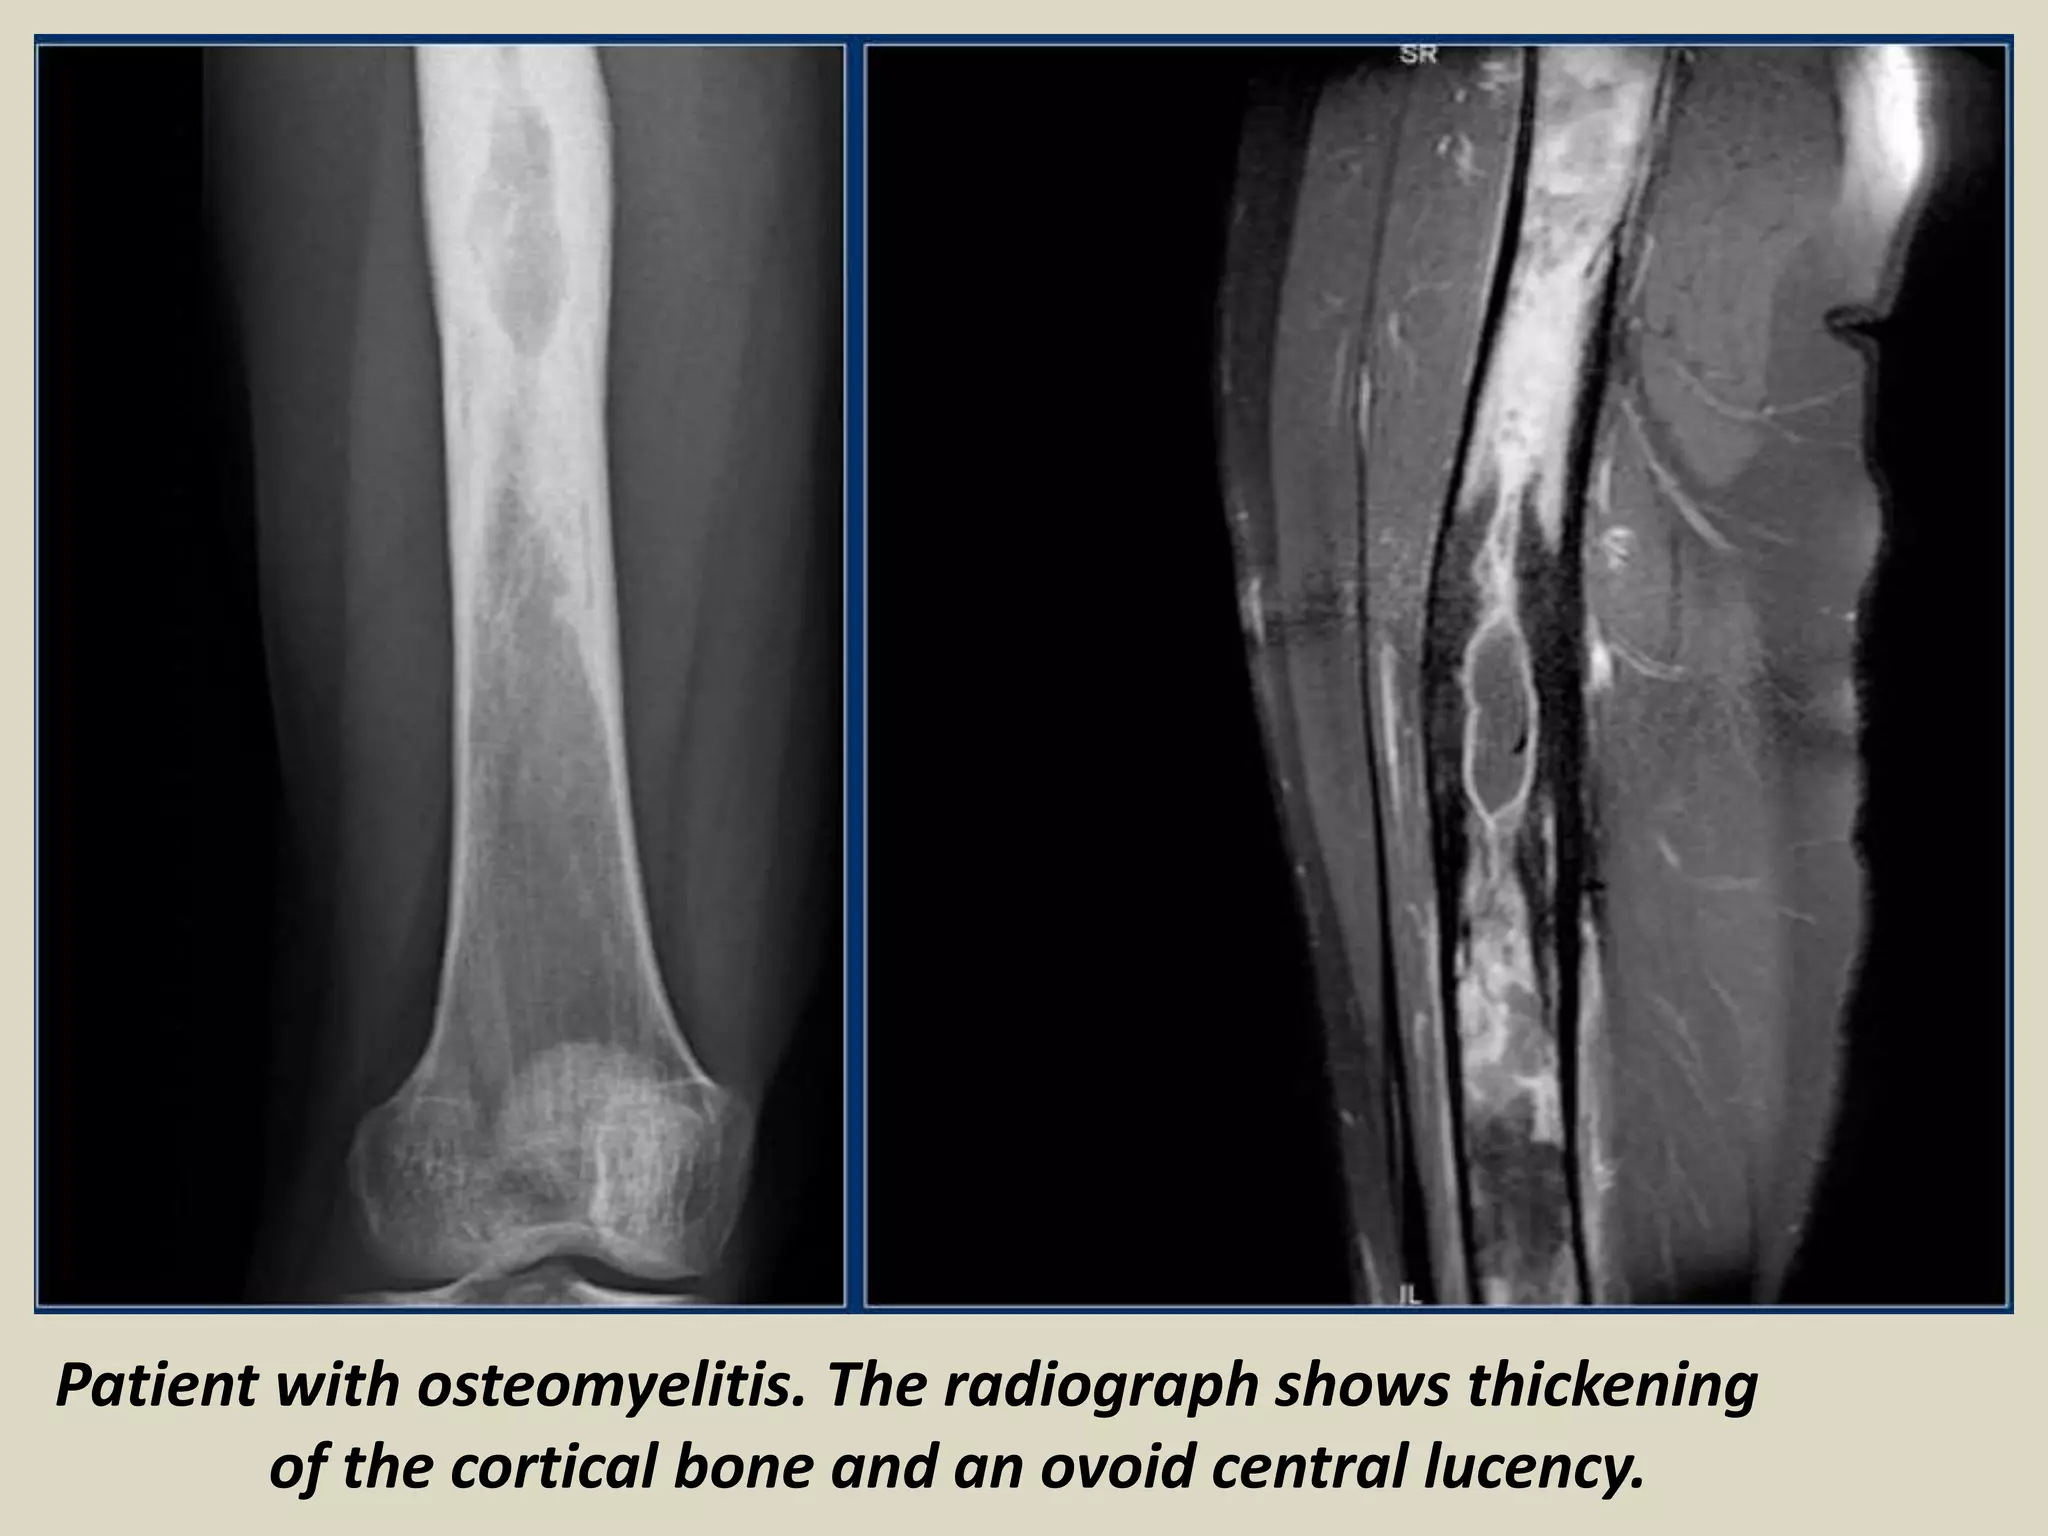

Patient with osteomyelitis. The radiograph shows thickening

of the cortical bone and an ovoid central lucency.

Radiology:

Lytic focus of bone destruction with peripheral zone of sclerosis and reactive

periosteum.

MRI: increased signal intensity in the medullary space.